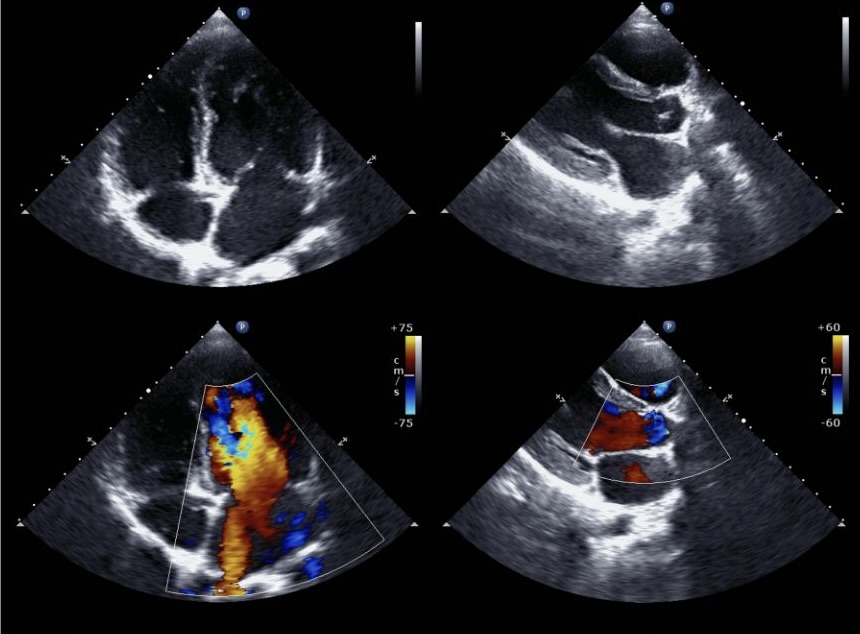

Eine Echokardiografie, oft als "Echo" bezeichnet, ist die Ultraschalluntersuchung des Herzens. Sie liefert detaillierte Informationen über die Struktur und Funktion des Herzens. In diesem Artikel zeige ich auf, warum die Echokardiografie neben dem EKG die wichtigste nicht-invasive Diagnostik in der Kardiologie ist.

Die Echokardiografie ist eine zentrale Diagnostik bei allen kardiologischen Fragestellungen und wird deswegen breit angewendet. Sie in den allermeisten Fällen medizinisch sinnvoll und sollte in der Abklärung von Herzbeschwerden durchgeführt werden.